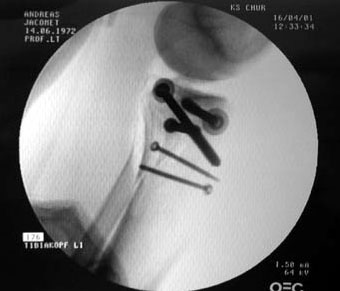

Belastet werden darf die ganze Konstruktion allerdings nicht, zumindest sechs Wochen lang - Titan und Edelstahl zierten für die nächsten Monate das Schienbein; ans Tageslicht kamen die erstaunlich grossen Schrauben erst im November wieder. Die folgenden Bilder wurden während der Operation gemacht: